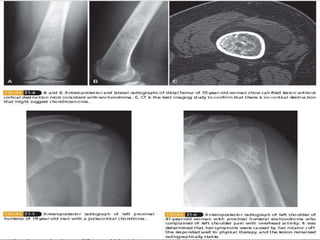

 More developmental malformations than true

neoplasms

 Originate within the periosteum as small

cartilaginous models

 Slight male predominance. 2nd-3rd decade.

Metaphysis of long bones

 Multiple hereditary exostoses (MHE) is

autosomal dominant —mutation of EXT1 or

EXT2

 Presentation - Mass; may be painful

secondary to irritation of soft tissue

structures, fracture, or overlying bursa.

 Two types – Pedunculated or Sessile.

Pedunculated more common.

 Imaging studies – Plain radiograph/CT/MRI

(Confirmatory) – Pedunculated or sessile

bone lesion that communicates with the

intramedullary canal of the host bone +

Cartilage cap

 Histological features – Similar to epiphysis of

the bone which undergoes enchondral

ossification

 Treatment – Observation if asymptomatic

En bloc resection – if symptomatic, with

removal of the cartilage cap.

 Malignant degeneration – rare – 1% solitary,

5% in multiple hereditary exostoses.